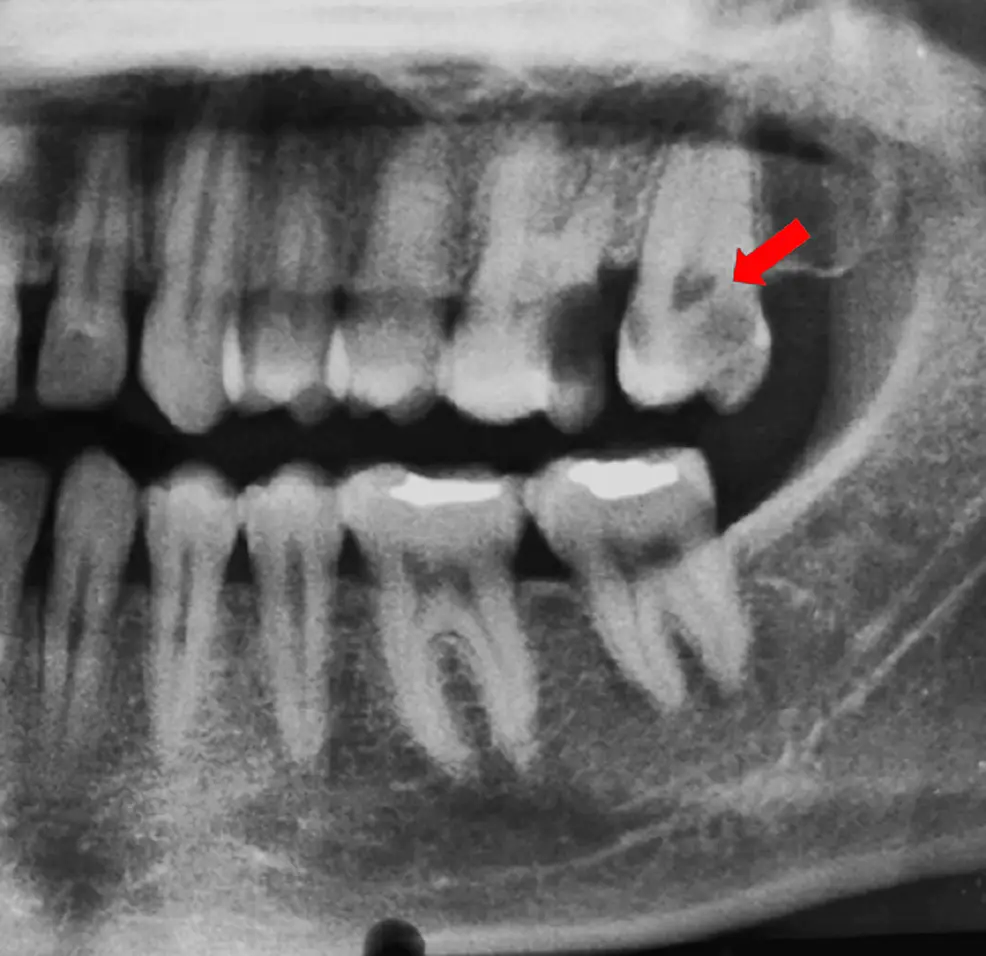

3. Phân loại Fan: Tiêu chuẩn vàng trên hình ảnh CBCT

Việc phân loại dựa trên hình ảnh 3D (Fan et al.) giúp bác sĩ lập kế hoạch điều trị chính xác hơn so với các phương pháp truyền thống:

C1 (Liên tục): Ống tủy hình chữ C không bị gián đoạn, khó làm sạch nhất do diện tích bề mặt lớn.

C2 (Dấu chấm phẩy): Có sự gián đoạn nhưng các góc hình học vẫn duy trì sự kết nối lớn.

C3 (Chia tách): Hai hoặc ba ống tủy riêng biệt nhưng được nối bởi các eo hẹp.

C4 (Đơn chiếc): Chỉ một ống tủy tròn hoặc oval.

C5 (Vắng mặt): Thường gặp ở vùng chóp do vôi hóa.

Lưu ý quan trọng: Hình thái ống tủy không cố định mà biến thiên liên tục từ miệng ống tủy đến chóp răng. Chỉ 19.2% số răng giữ nguyên một dạng phân loại suốt chiều dài chân răng.